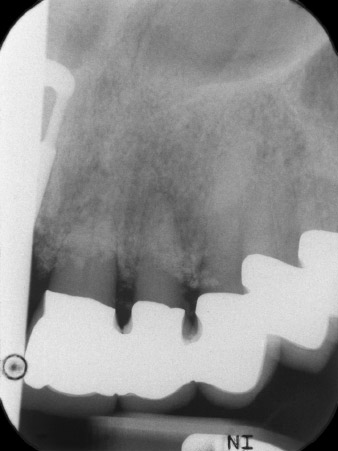

pilot drilling is performed with the new Implantmed and the WS-56 L contra-angle handpiece

Fig. 2: Two months later the pilot drilling is performed with the new Implantmed and the WS-56 L contra-angle handpiece (programme P1, ratio 1:1). The cooling is performed via the spray tube positioned on the left (for right-handed users).